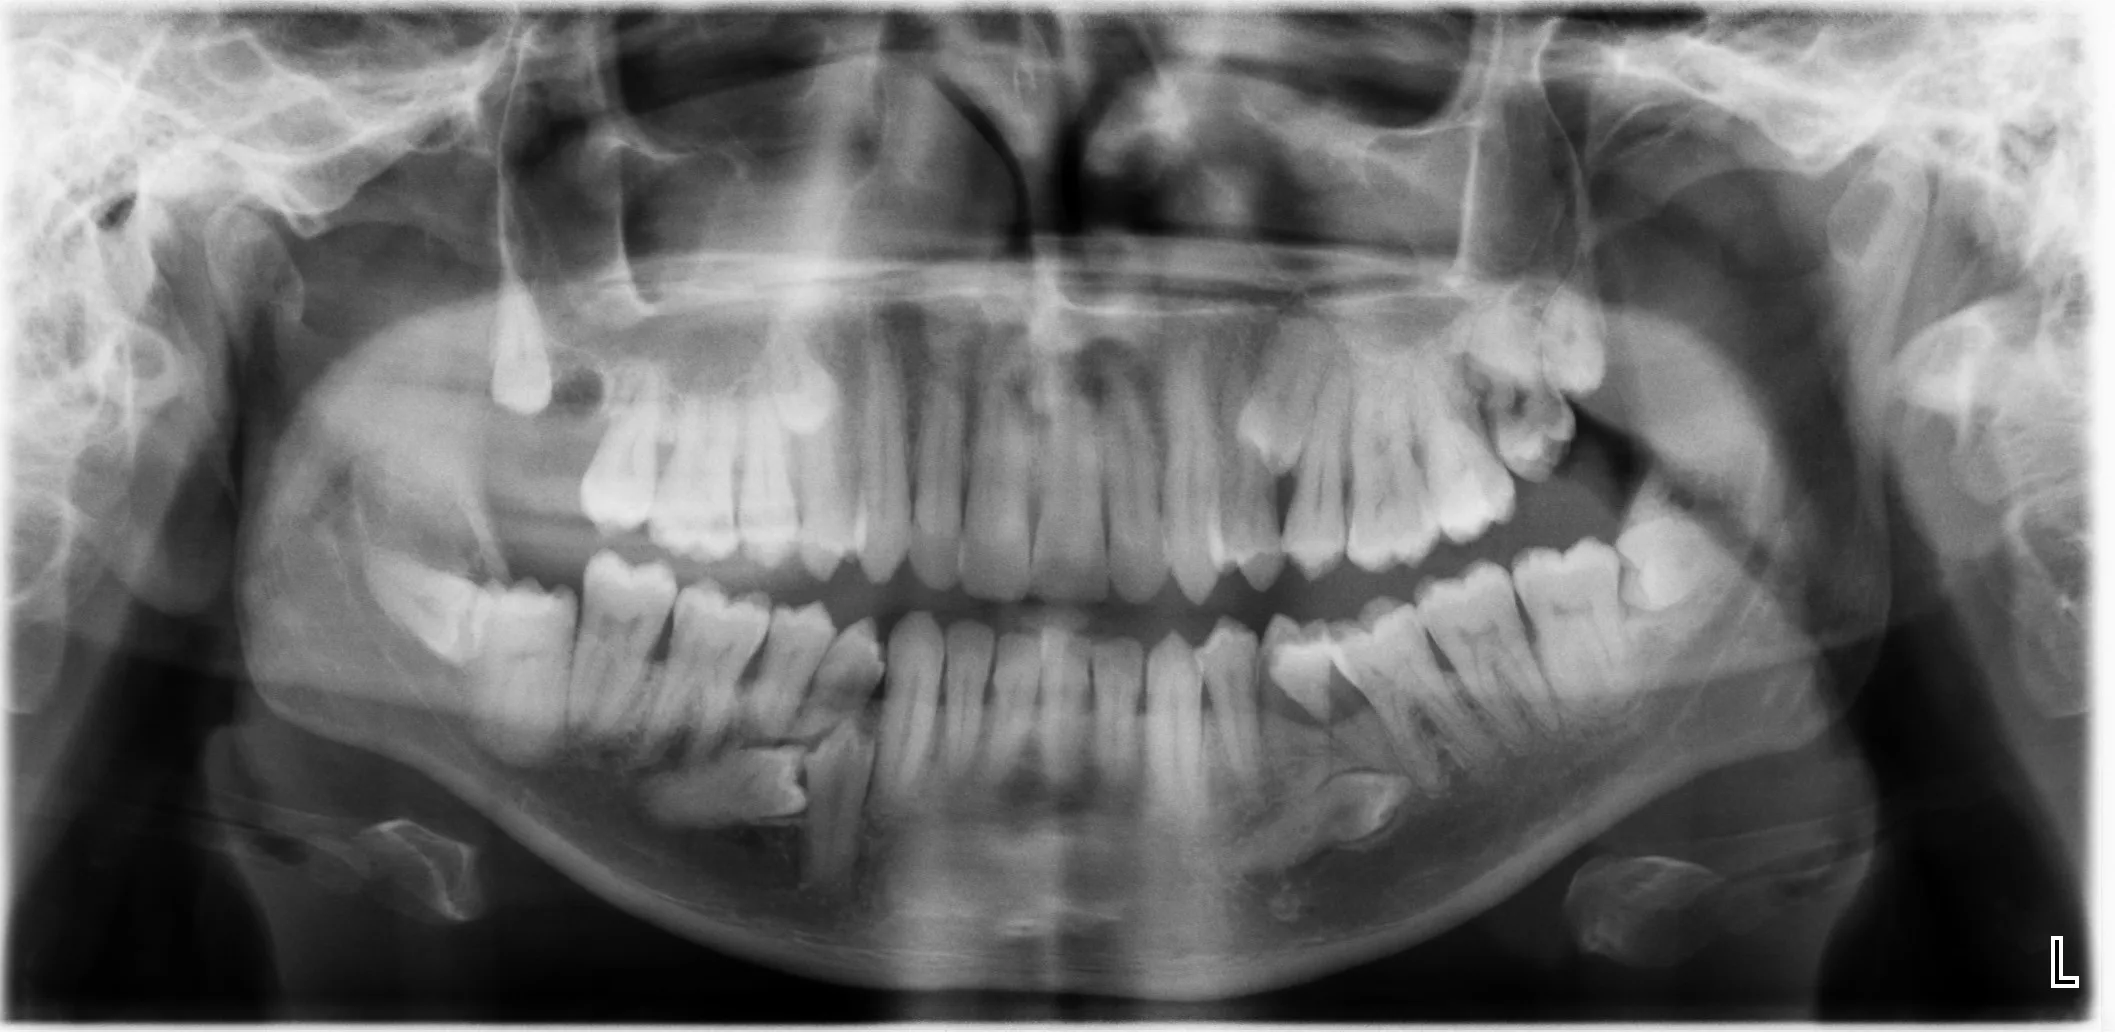

CBCT Scans & Reporting

Services delivered through Prime Health - Weybridge